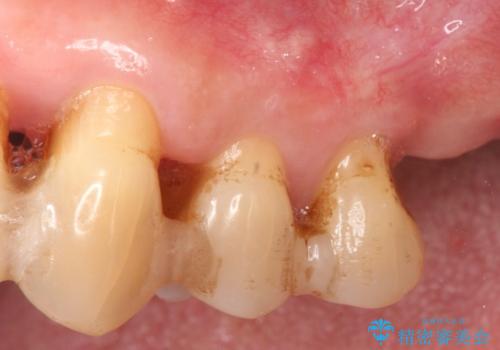

- 夜間のくいしばり、はぎしりが激しく全体的な歯周病が進行し、治療を希望され来院されました。

歯周ポケットの徹底的な除去を行なったのち、歯の揺れを抑え、過大な力がかからぬよう連結クラウン(歯周補綴)を行い強大な力に対抗します。

- 55万円(仮歯×3・ファイバーコア×3・歯周外科)費用は治療当時の料金となります